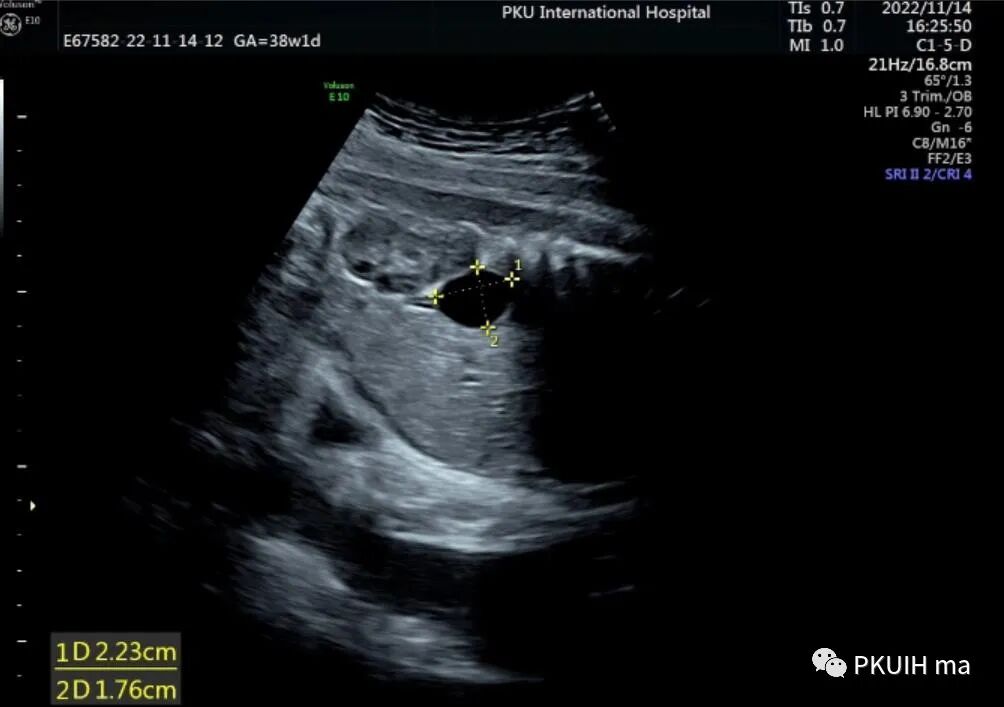

胎儿腹部囊肿在临床中是比较常见的,发生的部位有肝、胆道、肾、肾上腺、胃肠、卵巢、子宫及阴道等。在诊断异常时首先需要认识正常结构,因胎儿腹部内有许多结构表现为囊性的。对于囊肿的诊断首先要确定囊肿发生的部位。肾上腺区囊性占位并不罕见,临床中最常见的就是肾上腺出血性囊肿、单纯囊肿或成神经细胞瘤囊性变。肾上腺区的囊肿相对于腹腔其它部位囊性占位的鉴别比较容易,下面看看几个病例孕妇之前超声检查均正常,于38周发现右肾上极前内侧见一囊肿回声,大小约2.2x1.8cm,囊内透声好,其内未见血流信号。囊肿下方似见部分肾上腺组织。生后超声检查考虑肾上腺囊肿,随访至六个月囊肿无变化。新生儿目前无异常,一直在定期随访中。